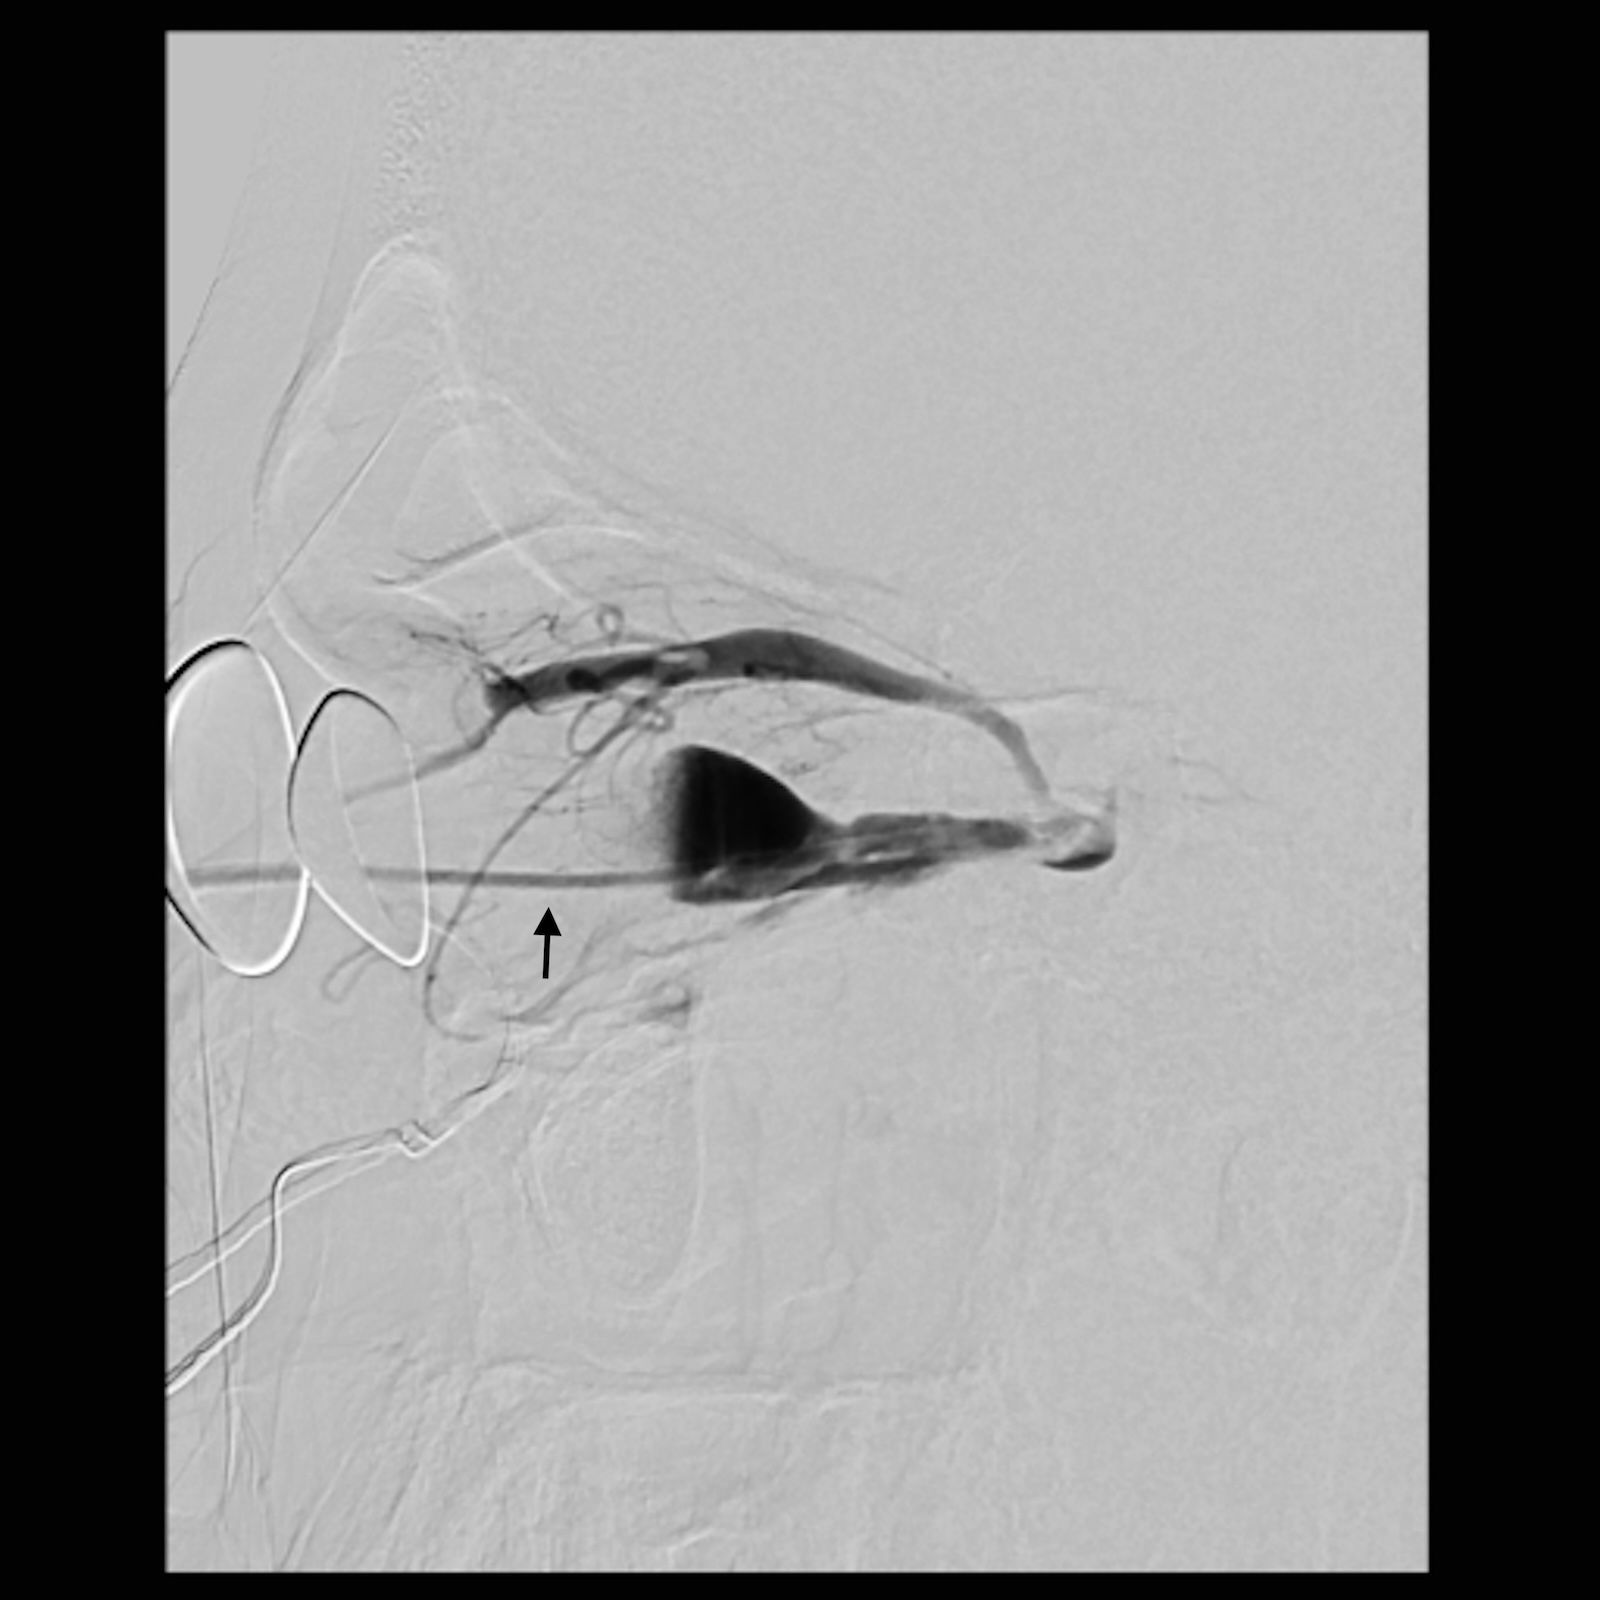

An angiographic image showing a catheter inserted into a curved blood vessel. A contrast medium highlights the vessel, and an arrow points to a specific area of interest.

Figure 6. Lateral view of the angiogram after coiling of the venous outflow tracts of the fistula demonstrating complete occlusion of the outflow tracts. Arrow indicates location of coils.

A multi-disciplinary surgical plan was developed. The patient underwent left medial orbital decompression to decompress the optic nerve, decongest the orbit, and provide access to the venous bulb of the fistula. This was followed immediately by cannulation of the venous anomaly in the operating room using a 5-French micropuncture sheath under direct intraoperative observation (Figure 5), followed by transfer to the fluoroscopy suite. With intraoperative angiography providing a “road map”, the venous outflow channel to the SOV was embolized with 20 coils, revealing a second outflow channel. The orbital catheter was manipulated and repositioned to access the second channel, which was then embolized with another 18 coils. At this point, the venous component was noted to have venous stasis (Figure 6), which would promote clotting followed by involution of the venous anomaly. The SOV was preserved and patent. Given the potential for a compartment syndrome, a lateral canthotomy and a cantholysis were performed preemptively to preserve normal intraocular and intraorbital pressure in the immediate post-operative period.